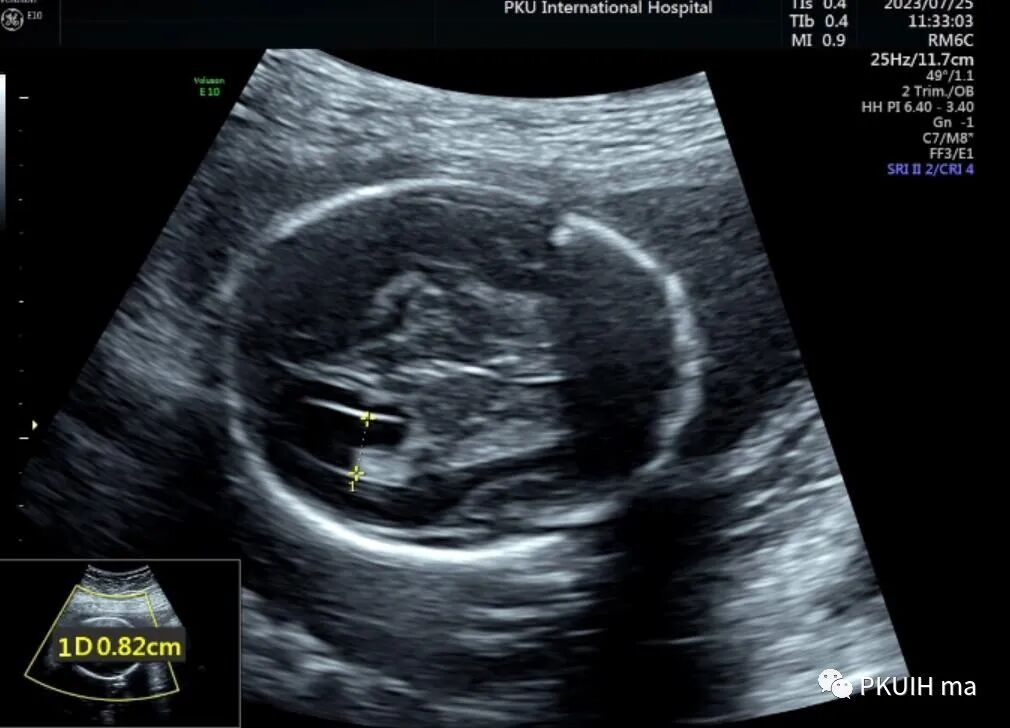

昨天看了一个孕妇,透明隔腔比较细窄,由于胎儿姿势不好和孕妇较胖做了四次也没有很好的完成胎儿神经系统筛查,打算过几天再看。

胎儿透明隔腔比较小(内径约1.6mm),透明隔存在,与侧脑室前角无相通,韦氏腔也比较小只有2.4mm

侧脑室看着也还可以没有发现有明显泪滴状,透明隔腔下方穹窿也存在,于是想着先看下胎儿胼胝体